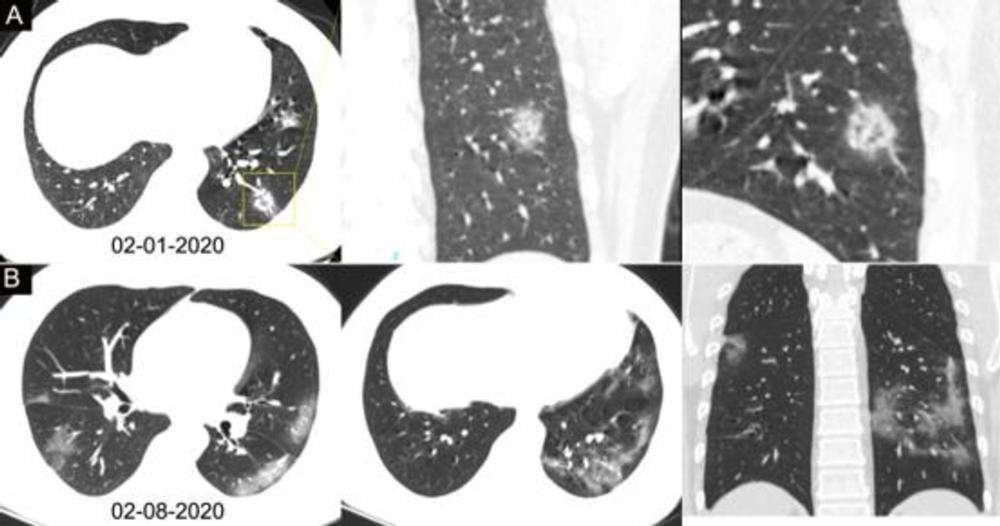

Ciddi vakaların çoğu, akciğerlerdeki hava boşluklarının iltihaplanması ile karakterize edilen bir durum olan pnömoniden kaynaklanıyor. Bu iltihap, akciğerin hava keselerinin sıvı ve hücrelerle dolmasına neden olarak nefes darlığı, düşük oksijen seviyeleri ve öksürüğe neden olabiliyor. Bunun sonucunda, kan dolaşımına yeterince oksijen ulaşmayabiliyor.